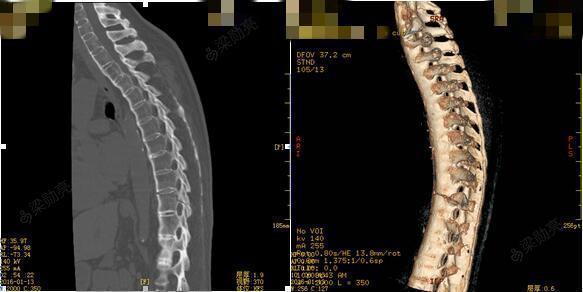

脊柱休门氏病scheuermannsdisease

图片尺寸1080x1220